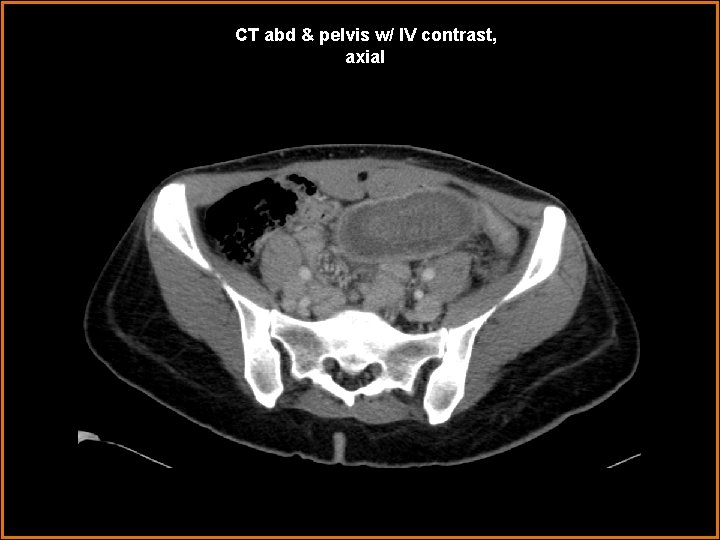

Case History 42 year-old female status-post gastric bypass operation within the last year presents with acute abdominal pain, nausea, and vomiting, for two days.

CT abd & pelvis w/ IV contrast, axial

Findings and Differentials Findings: -- several centimeters of small bowel lumen-within-lumen appearance—“target / bull’s eye” appearance, in axial cross-section -- mesenteric fat and vessels enter at the most proximal end of this small intestinal “telescoping” -- dilated immediate distal or outer aspect of the telescoping bowel-in-bowel segment -- however, decompressed distal small bowel and decompressing colon -- surgical anastomotic small intestinal clips in mid abdomen nearby segment of jejunum enters a segment of distal jejunum, near a post-operative site Differentials: • Intussusception • Midgut volvulus

Diagnosis Jejuno-jejunal intussusception, with partial small bowel obstruction converting to completion